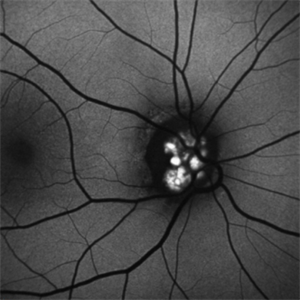

Optic Disc Drusen Autofluorescence

Apr 2 2016 by David Callanan, MD

30-year-old Caucasian male with visual field defect OD > OS.

Condition/keywords: optic disc drusen